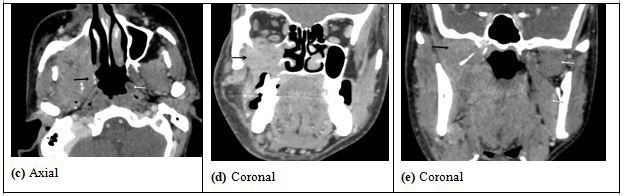

| Figure 8: (c) The lesion is extending to involve the right lateral wall of nasopharynx with obliteration of Eustachian tube and fossa of Rosen Muller (black arrows).

Compare with normal left lateral wall of nasopharynx (white arrows) (d) Bony erosion of the right side of hard palate and erosion of floor of right orbit with intra-orbital extra-conal extension abutting the inferior rectus muscle and inferior oblique (e) In the infra-temporal fossa there is involvement the right medial pterygoid and lateral pterygoid muscles (black arrow). Normal left medial pterygoid and lateral pterygoid muscle (white arrows) |